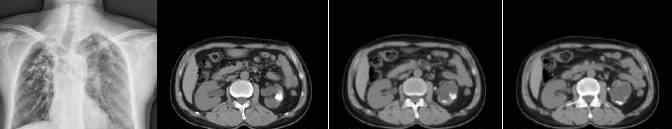

胸片+上腹部平片+静脉尿路造影(IVP)

胸片未见明显异常。上腹部平片扫描发现双肾有多个厚壁囊性肿块。低密度区的CT值约为8-12HU,右肾皮质变薄,左肾盂、肾盏和输尿管肿胀,左输尿管壁增厚。IVP显示左侧肾盂和肾盏扩张,左侧输尿管扩张。右尿路整个过程没有明确的发展,提示右肾功能下降或丧失。

辅助检查:ESR 42mm/h;结核分枝杆菌直接检测(MTD):阳性。

最终诊断:双侧肾结核伴左侧肾盂、肾盏及输尿管积水;左侧输尿管壁稍增厚,考虑结核侵犯输尿管壁。